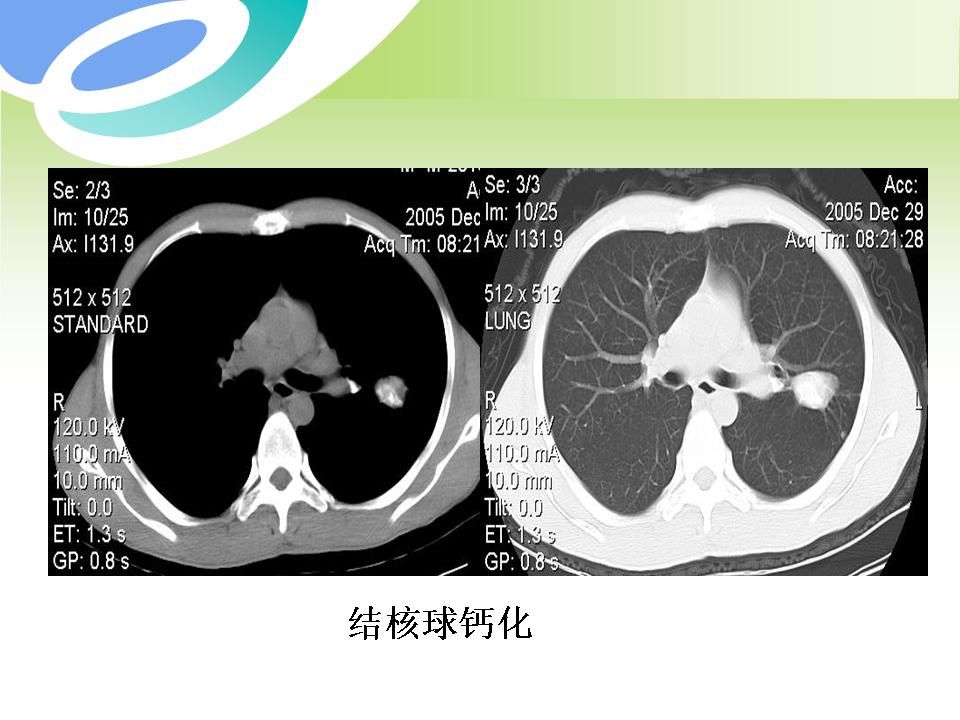

肺部病变的CT基本征象